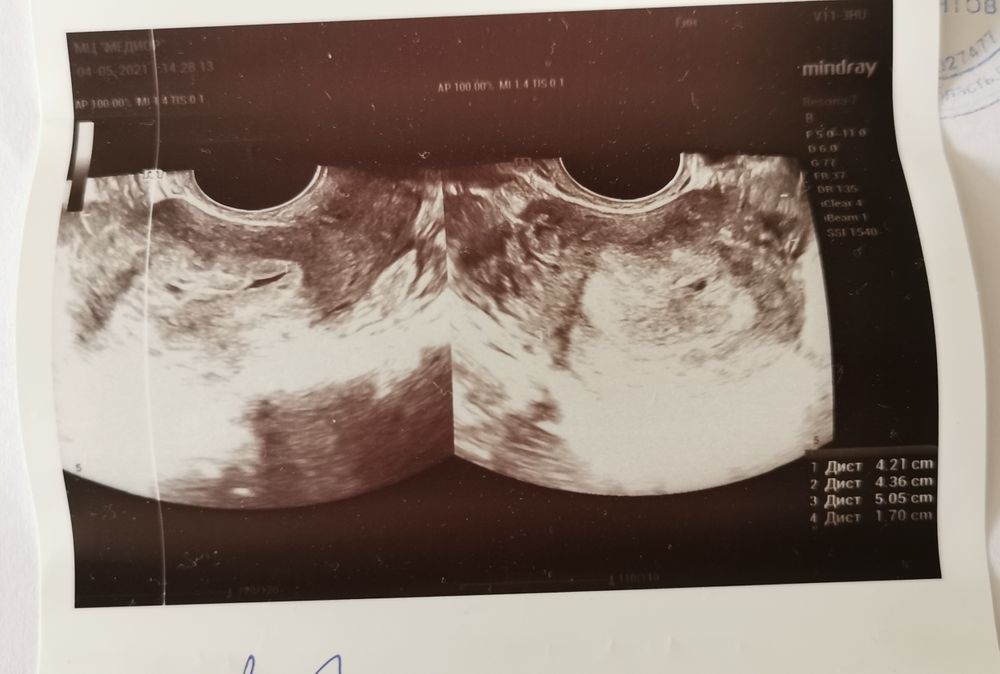

4 мая узи - пя в матке не нашли, в трубах тоже нет, жт есть(размеры не написала), энд 17 мм, кровь в матке 15*2мм, поставила зб на раннем сроке